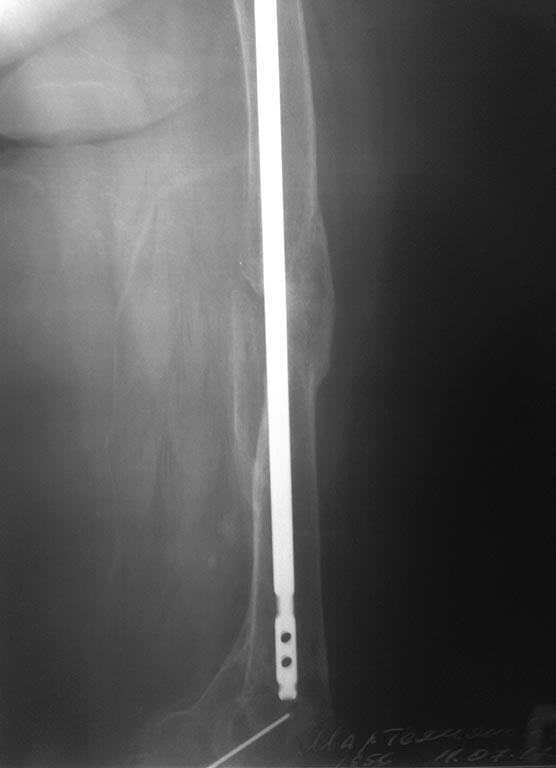

здравствуйте уважаемые коллеги. нужна помощь в дальнейшей тактике по пациентке 62 года вес около 90 кг . передвигается при помощи костылей .

В 2011 году остеосинтез правого бедра на данный момент ложный сустав шейки правого бедра. что бы отправить на ВМП нужно удалить металл, боимся за диафиз бедра. как поступить и кто сможет помочь?

Реостеосинтез ретроградным стержнем. Снимков мало.

Действительно, и ждать, пока окрепнет в области диафиза, можно годами. И если заранее удалять - может ослабленный диатез сломаться, и в условиях болтающегося диафиза уже никто ни на какую ВМП не поедет.

Поэтому оптимально заранее договориться с тем центром, куда пациент поедет для замены сустава, чтобы сделали в одну сессию. И обеспечить коллегам заранее всю информацию - что за железка, и где взять инструмент для удаления.

И для планирования, конечно, этого одного снимка мало - надо все бедро видеть, и зону бывшего перелома особенно хорошо. То ли там схватилось, то ли надо сразу планировать длинную ревизионную ножку, чтобы перекрыть эту зону.

еще снимки

Мозоль достаточно мощная, не должно быть никаких проблем после удаления.

Оптимальный вариант - все сделать в одну операцию. Но если это невозможно организационно, можно удалить стержень. Пациентка ходит на костылях - полной нагрузки не будет из-за ложного сустава шейки. Если после эндопротезирования возникнет подвижность на уровне диафиза - остеосинтез пластиной и костная пластика. Если подвижность возникнет сразу после удаления стержня - все сделать в обратной последовательности (пластина, костная пластика, протез). Безусловно, наличие ревизионной ножки расширило бы возмозможности решения проблемы.

Что с коленным суставом? Судя по снимкам, можно предположить наличие гонартроза. Если это так, то абсолютно беспроигрышным вариантом представляется тотальное интрамедулярное замещение бедренной кости, гвоздь удаляется в эту же сессию. Имеем три в одном: искусственный тазобедренный сустав, искусственный коленный, риск перипротезного перелома исключён. Конечно вопрос бюджета